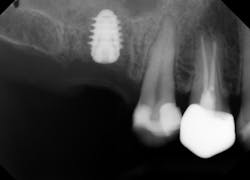

As direct implant costs have gone down, the simplification and efficiency of many implant procedures have contributed to what many are calling the “golden age of implant dentistry.” The advent of short implants—and research articles backing the success rate of short implants—has reduced the need for more extensive grafting procedures. This is one clinical area that has allowed more general practitioners to place more implants due to the simplified sinus-area procedures. In areas of 6 mm or more of maxillary bone height, clinicians are able to provide a minimally invasive sinus bump and achieve bicortical stabilization. Implants such as the iHex and MorsTorq were designed with a rounded end to safely provide this procedure. The taper of these and similar systems also protects the implant from being lodged apically into the sinus cavity, thus making it user-friendly for beginner to intermediate implantologists.

Therefore, if a patient has 5 mm of available bone height from the sinus floor, a maximum of 5 mm is prudent to expect from an indirect lift; therefore, an 8 mm to 10 mm implant is the ideal choice. The tapered iHex or MorsTorq implant provides safety when dealing with sinus areas, for three reasons. First, the taper helps prevent overinsertion toward the sinus cavity. Second, the abutment and transfer attached to the implant allows for more control. Finally, the rounded apex helps reflect the sinus floor without creating damage (figures 1-6).

Admittedly, there is some technique sensitivity in relation to both the open sinus and closed sinus lift procedures. A recent article about tapered implants placed in maxillary sites with residual bone height of 1 mm to 6 mm reported high success rates using a closed technique without grafting material, which led to bone formation beyond the original limit of the sinus floor.2